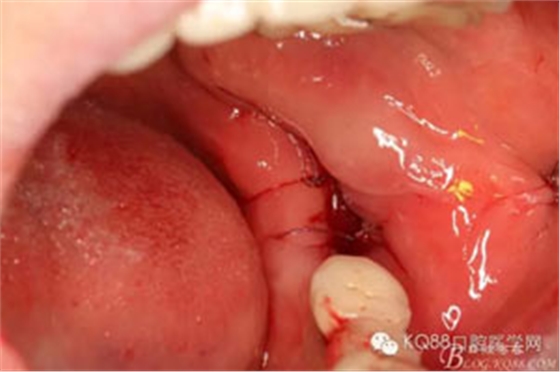

圖10. 放膠質(zhì)銀止血海綿。

圖11. 可吸收性縫線縫合